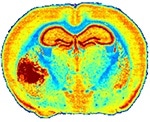

Left: A mouse brain tissue section analysis by IR microscopy showing the anatomical details of brain with tumor (left part) based on extracellular matrix distribution. FTIR acquisition lasted 12h for a 20-µm resolution while QCL-IR acquisition could be done in 1h50 with a 4.4-µm resolution.

The image shown is down-sampled by 8x8 due to file size limitations.